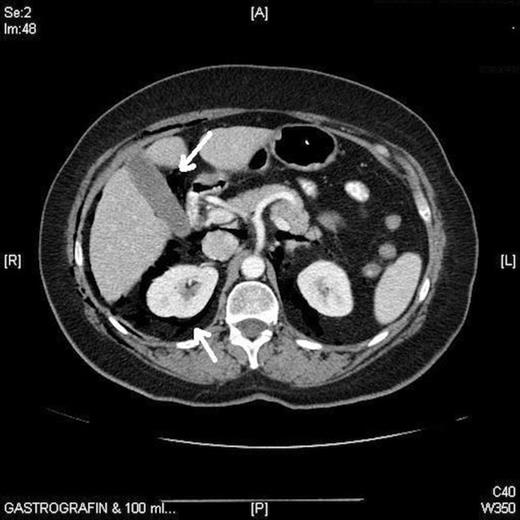

Full blood count was normal and a chest radiograph on admission showed subcutaneous emphysema, pneumo-mediastinum and pneumopericardium but no other abnormality (fig. 1). Computerised Tomography of the abdomen showed in addition, pneumoperitoneum and pneumoretroperitoneum (fig. 2). A water-soluble contrast examination of the colon failed to reveal evidence of a colonic perforation.

CXR showing subcutaneous emphysema, pneumomediastinum and pneumopericardium